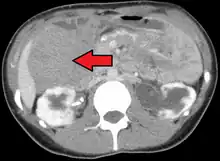

| Desmoid tumor as seen on CT scan | |

MRI or CT imaging scans are commonly used for monitoring.[47][1]